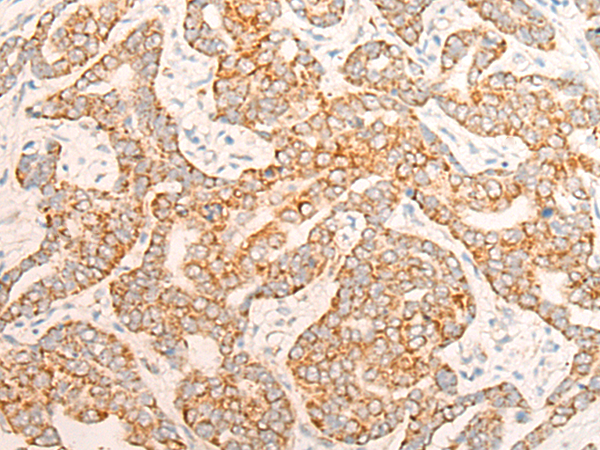

- The image is immunohistochemistry of paraffin-embedded Human liver cancer tissue using P13127(ALDH7A1 Antibody) at dilution 1/20. (Original magnification: ×200)